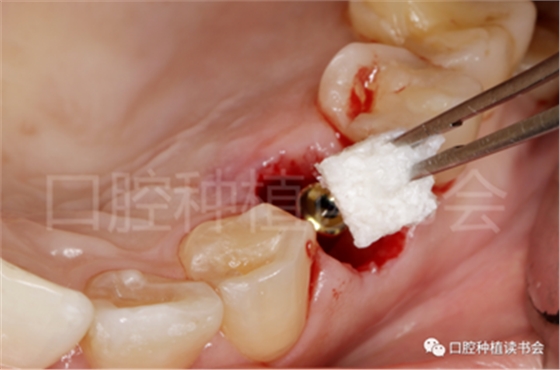

5.3.4 旋入覆蓋螺絲,在種植體與四周骨壁的間隙內(nèi)植入 Bio-Oss Collagen,植骨材料用生理鹽水濕潤(rùn)后,用15#刀片分割為小塊分別植入,并用充填器壓實(shí)(圖17)。

圖17 后牙即刻種植植骨推薦使用骨膠原材料,有利于軟組織愈合。

5.3.5 考慮到初始植入扭矩未達(dá)到30N.cm,采用外覆”倍菱“膠原蛋白+縫線固定的方式關(guān)閉創(chuàng)口的方案(圖18)。

圖18 創(chuàng)口使用”倍菱“膠原蛋白保護(hù),促進(jìn)愈合。